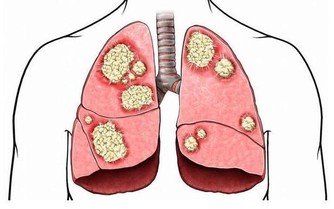

7、經常咳嗽,或支氣管、肺部等發炎;

硒是人體不可或缺的微量元素,幾乎存在於所有免疫細胞中。一旦缺乏,會導致免疫力下降,甚至增加癌症風險。